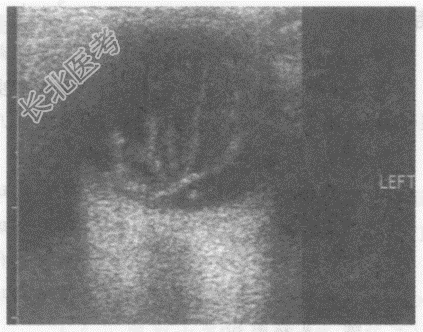

- 单项选择题女,66岁, 自诉左眼视物不清。超声综合描述:左眼玻璃体透声不清亮, 可见较多中强回声光带,可随眼球运动而移动。超声提示:

A、脉络膜脱离

B、视网膜脱离

C、玻璃体积血

D、玻璃体机化膜

E、球内异物